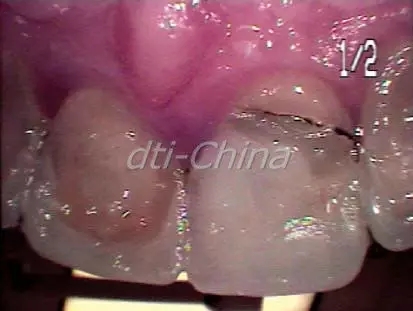

這是一位30多歲的健康男性,在我的診所檢查到右側(cè)上頜中切牙折斷,患者幾年前上中切牙和側(cè)切牙已經(jīng)使用長石質(zhì)陶瓷進行了修復,他的這顆前牙有運動創(chuàng)傷的病史,并且做了根管治療。上頜切牙近期的根尖片顯示內(nèi)吸收(圖5),這名患者右側(cè)上頜中切牙因為跌倒持續(xù)創(chuàng)傷導致冠的完全折斷(圖6),這牙齒不能復原。患者對不同治療方案的進行評估后,決定進行即刻種植修復。考慮到在美學區(qū)相鄰種植體植入會導致牙齦組織結(jié)構不良,盡管左側(cè)上頜側(cè)切牙也顯示內(nèi)吸收,但患者還是決定稍后再處理這顆牙。牙周醫(yī)生對于右側(cè)上頜中切牙的即刻種植手術進行了評估,這名患者的治療跟第一個病例的患者相同。右側(cè)中切牙被拔除,Nobel Replace Tapered Groovy (內(nèi)連接) 5.0 mm x 13 mm植體植入,利用一個凍干脫鈣骨移植物和一個膠原膜對手術位點進行骨移植增量。愈合基臺維持基本輪廓,患者即刻獲得一個非功能性的臨時冠。